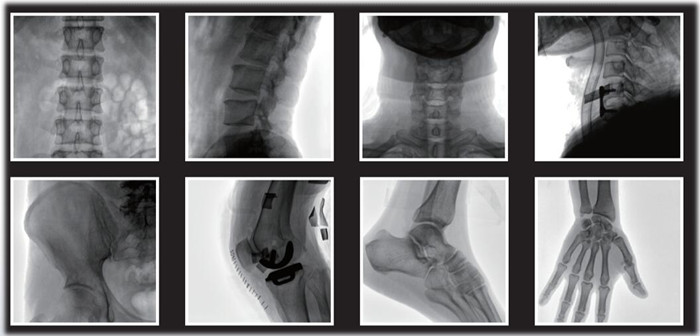

1)小C,骨科手術(shù)必備設(shè)備,也被稱為骨科小C。作為骨科醫(yī)生的眼睛,能在手術(shù)中透視實(shí)現(xiàn)準(zhǔn)確定位,輔助醫(yī)生順利、快速、高效完成手術(shù)。目前,小C在我國普及率極高,基本上所有二級及以上醫(yī)院都標(biāo)配小C。

小C在骨科的應(yīng)用是全方位的